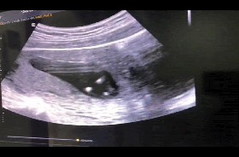

12weeks อัลตราซาวน์เห็นเพศ

วันนี้ครบ 12สัปดาห์ หมอบอกน่าจะเป็นผู้ชายแต่ไม่ชัวร์ เอาภาพอัลตราซาวน์มาให้แม่ๆช่วยดูกันคะ